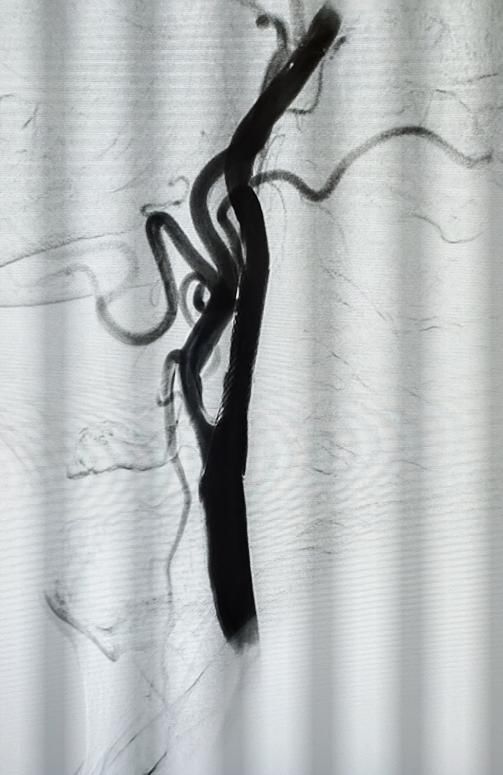

患者行颈部血管彩超发现颈动脉蹼,行脑血管造影发现右颈内动脉C1段管腔狭窄约70%,重度狭窄遇到变异的颈动脉蹼更容易导致脑缺血,引起脑梗死。

(术前造影显示有小面积脑梗)

术后右侧颈内动脉狭窄较前改善明显,右侧大脑前及大脑中动脉血管显影良好,患者安全返回病房。

(术后右侧颈内动脉狭窄较前改善明显)